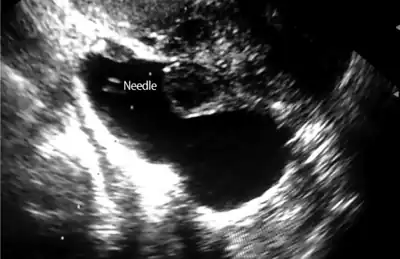

| Left hydrosalpinx on gynecologic ultrasonography | |

Hydrosalpinx may be diagnosed using ultrasonography as the fluid filled elongated and distended tubes display their typical echolucent pattern. However, a small hydrosalpinx may be missed by sonography. During an infertility work-up a hysterosalpingogram, an X-ray procedure that uses a contrast agent to image the Fallopian tubes, shows the retort-like shape of the distended tubes and the absence of spillage of the dye into the peritoneum. If, however, there is a tubal occlusion at the utero-tubal junction, a hydrosalpinx may go undetected. When a hydrosalpinx is detected by a hysterosalpingogram it is prudent to administer antibiotics to reduce the risk of reactivation of an inflammatory process.